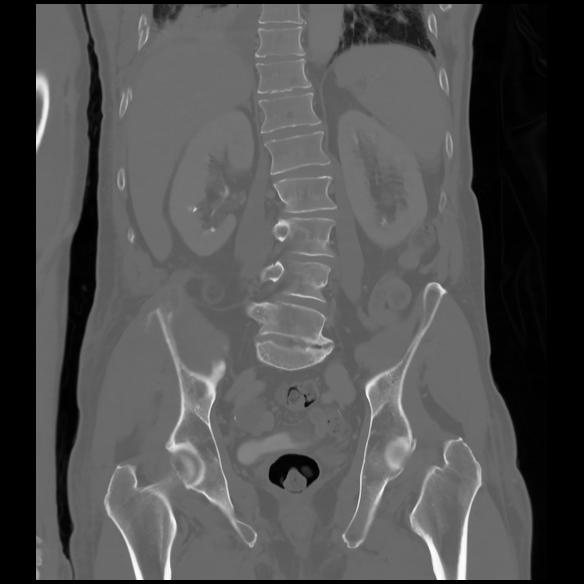

6 CUERPO,CE,Coronal,3.000,CUERPO,Coronal,